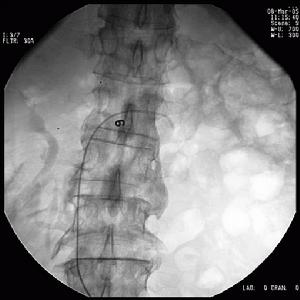

疾病檢查

腎活檢2、血清學檢查 初選試驗可包括抗核抗體(ANA)譜,抗雙鏈(ds)DNA,抗中性粒細胞胞漿抗體(ANCA),抗基底膜(GBM)抗體和抗磷脂抗體。SLE患者可有高滴度ANA和dsDNA,而補體水平降低。Goodpasture綜合徵的循環抗GBM抗體陽性。ANCA包括核周型(P-ANCA)和細胞漿型兩種,前者為針對髓過氧化物酶(MPO),彈力酶和乳鐵蛋白的抗體,後者針對的抗原為分布在細胞漿的絲氨酸蛋白3(PR3),即C-ANCA。顯微鏡下多動脈炎、Churg-Strauss血管炎和寡免疫性腎小球腎炎(PIGN)可出現P-ANCA陽性。

3、組織學檢查 活檢部位的選擇取決於具體疾病,如診斷韋氏肉芽腫,可進行鼻或鼻竇活檢,侵入性小診斷價值又高。

肺出血-腎炎綜合徵4、腎活檢 除了常規光鏡檢查外,通常需要進行直接免疫螢光染色。免疫介導的肺泡出血綜合徵同時有腎受累時,則腎病理為壞死性腎小球腎炎,組織學改變的程度不同,從輕的系膜增厚至嚴重的新月體性腎小球腎炎,腎動脈血管炎則很少。各種疾病的免疫螢光染色有不同表現,抗基底膜抗體(ABMA)病沿腎小球基底膜有線樣沉積,膠原血管病及特發性免疫複合物介導的腎小球腎炎呈顆粒狀沉積,而PIGN的免疫螢光檢測為陰性,聯合血清學ANCA、ABMA、ANA等檢測能夠提高對診斷、治療和預後的判斷意義。

5、氣管鏡檢查 肺泡出血患者可能沒有明顯咯血。氣管鏡和肺泡灌洗(BAL)檢查有助確診肺泡出血,排除感染和氣道局部病變引起的出血,從而幫助鑑別診斷和尋找病因。根據BAL的回收液血性程度逐漸增加,可肯定為活動性出血,此外,顯微鏡檢查發現含鐵血黃素細胞也具有肯定肺泡出血的價值。

6、肺活檢 經支氣管肺活檢對於DAH的診斷價值有限,為明確病因需開胸肺活檢。肺活檢僅適用於經常規檢查仍未明確病因,且病情相對穩定,能夠耐受單側肺萎陷的患者。嚴重肺出血和呼衰病人不適宜開胸肺活檢。肺活檢術後可伴發感染和氣胸。